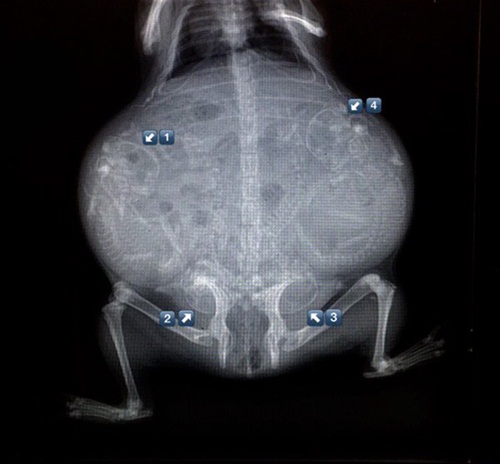

Bào thai chó.

Bào thai mèo.